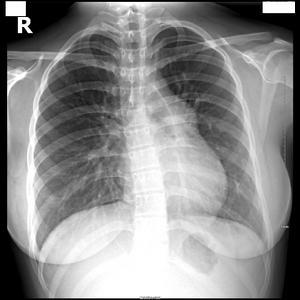

原发性肺动脉高压[1](primarypulmonaryhypertension)是一少见疾病,因其病因不明,而区别于继发性肺动脉高压。常见的初始症状如下:呼吸困难(60%),疲乏(73%),胸痛(47%),眩晕(41%),水肿(37%),晕厥(36%),心悸(33%)。